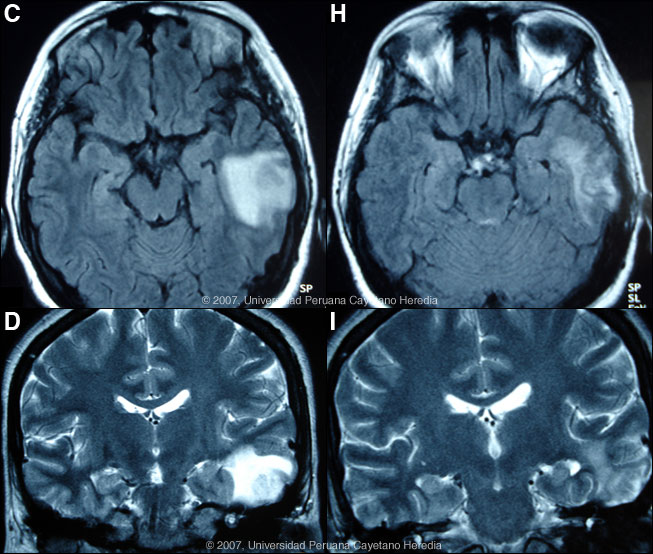

History: 21-year-old female patient first admitted 1 year earlier with painless papular lesions and a violaceous plaque on the right knee that that had been progressive over 4 years after trauma to that area. The patient had initially received empiric therapy over the years with oral fluconazole for approximately 45 days and then clarithromycin plus cotrimoxazole for 8 months with no improvement. A new papular lesion on the left thigh that evolved to a violaceous plaque developed 4 months prior to that admission. After a biopsy diagnosis was made, the lesions improved with 3 weeks of parenteral followed by continuous oral antimicrobial therapy. The patient was readmitted 3 months ago with a 2-month history of reactivation of the previous lesion on the left thigh, and the appearance of 2 new small papular lesions, 1 on the left breast and 1 on the dorsal chest area. No fever, chills, weight loss, or cough. Headache with no other neurologic complaints have developed during the current hospitalization. Epidemiology: The patient was born in Lima and lives in Lima. No history of travel to the jungle. There is no history of exposure to TB, no specific occupational exposures, and no history of swimming in brackish or contaminated fresh or sea water. Physical Examination: (on re-admission). Afebrile. Chest clear. No hepatosplenomegaly. Normal CNS exam. Skin lesion at initial admission is shown in Image A and at the beginning of the current re-admission in Image B. Laboratory Tests: (on re-admission). Hct 30, normal WBC with no eosinophilia. Normal liver function. Normal Chest X-ray. HIV and HTLV-1 negative. MRI is shown in Images C & D. A CT scan obtained elsewhere 4 months earlier was reported as normal. CSF contained 2 WBC (100% lymphs) with normal glucose and proteins and all stains were negative.

![]() Miltefosine is now established as effective anti-leishmanial therapy. A recent report showing good in vitro activity of miltefosine against Balamuthia, Acanthameba, and Naegleria [J Eukaryot Microbiol. 2006 Mar-Apr;53(2):121-6] led us to commence Miltefosine (150 mg/d for 12 days, then 100 mg/d chronically thereafter) and clarithromycin-cotrimoxazole-artesunate and amphotericin B were stopped as no clinical improvement was observed. After 37 days of miltefosine therapy, Image G shows partial healing of the skin lesions and the MRIs in Images H & I demonstrate significant improvement in the CNS lesion. The patient remains on miltefosine, fluconazole and albendazole. Unlike the patient we presented earlier this year [Gorgas Case 2007-06] who died rapidly after appearance of CNS disease, this patient has at least a short-term response to therapy.